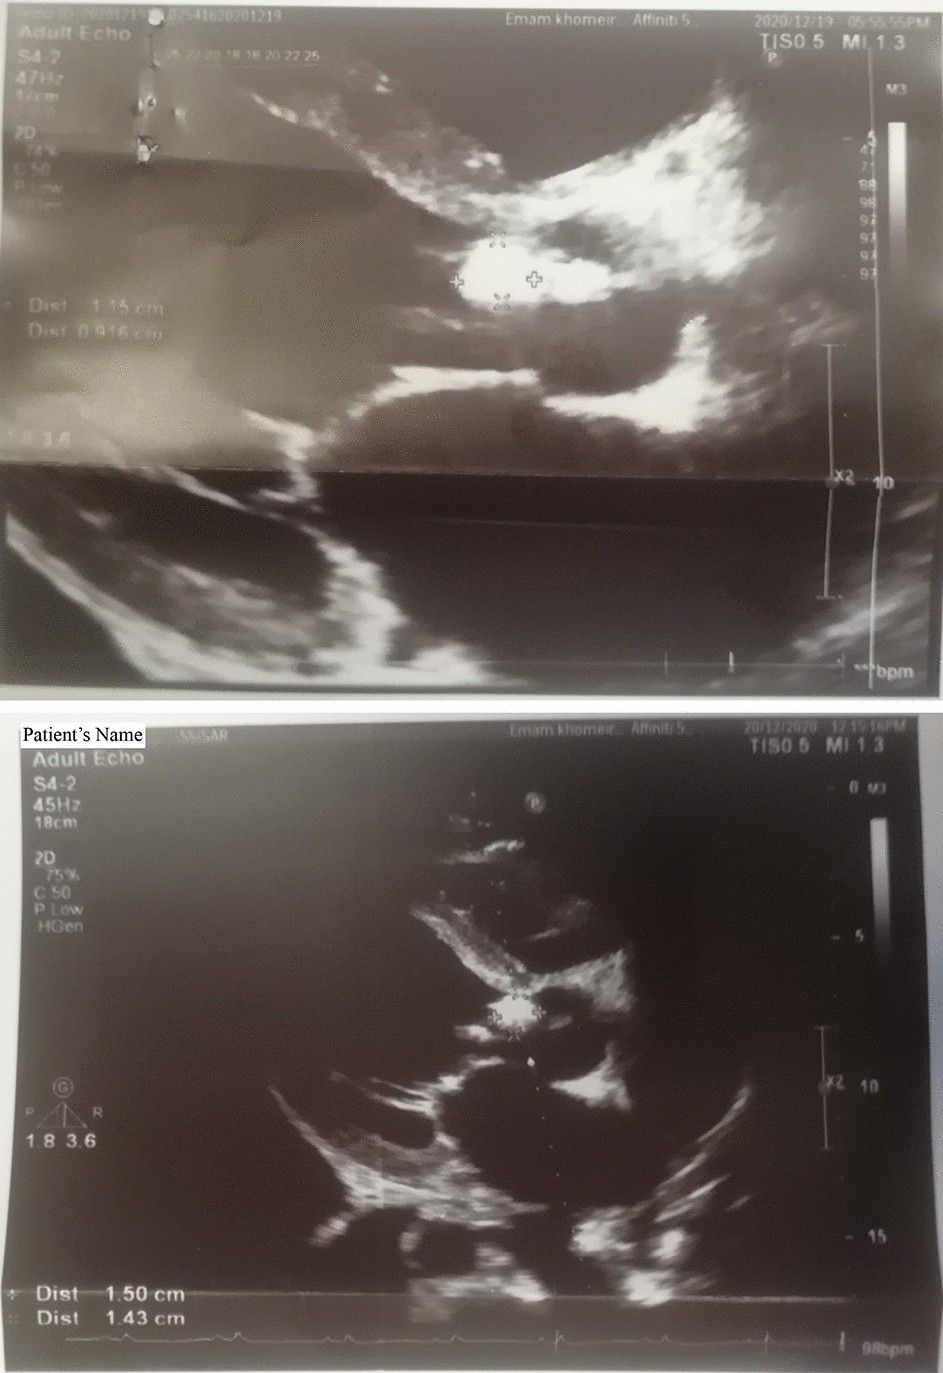

Fig. 1

Echocardiogram of Bartonella quintana positive patient. The vegetative mobile mass on the aortic valve is indicated by “+” sign.